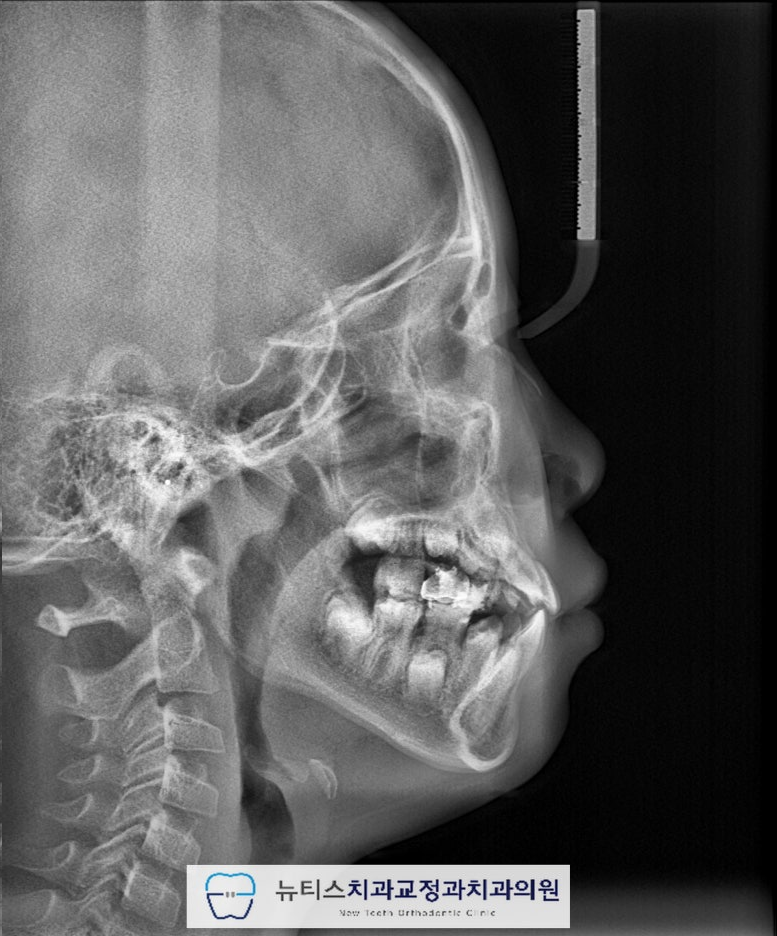

#ºÎ»ê¾î¸°À̹ݴ뱳ÇÕ ÀÌ °³¼±µÇ¾ú°íÀüÄ¡ºÎÀÇ ±³ÇÕ°ü°è°¡ ¾çÈ£ÇØ Á³½À´Ï´Ù. Ä¡·á ÈÄ ¹æ»ç¼± »çÁø¿¡¼µµ¹Ý´ë±³ÇÕÀÌ °³¼±µÈ °ÍÀ¸·Î È®ÀÎÇÒ ¼ö ÀÖ½À´Ï´Ù.(Ä¡·á±â°£ 6°³¿ù)  Ä¡·á Á¾·á ÈÄ 1³â Áö³ »çÁøÀÔ´Ï´Ù. #ºÎ»ê¾î¸°À̱³Á¤Ä¡°ú ÀÎ ÀúÈñ ´ºÆ¼½º¿¡¼´Â¹Ý´ë±³ÇÕÀ» °³¼±ÇÑ ÀÌÈÄ, À¯Áö°¡ Àß µÇ´ÂÁö ´Ù¸¥ ¹®Á¦°¡ ¾ø´ÂÁö ÁÖ±âÀûÀΠüũ¸¦ ½ÃÇàÇÕ´Ï´Ù. ÃÊÁø, Ä¡·á ¸¶¹«¸®, 1³â À¯Áö üũ »çÁøÀÔ´Ï´Ù. Àß À¯Áö°¡ µÇ¾ú°í ÀûÀýÇÑ ½Ã±â°¡ µÇ¸é2Â÷ ±³Á¤À» ÁøÇàÇÒ ¿¹Á¤ÀÔ´Ï´Ù~ #ºÎ»ê¾î¸°À̹ݴ뱳ÇÕ ÀÇ °æ¿ì¿¡´ÂÄ¡·áÀÇ Å¸À̹ÖÀÌ Áß¿äÇϱ⠶§¹®¿¡ Àü¹®°¡¿Í »ó´ãÇÏ´Â °ÍÀÌ Áß¿äÇÕ´Ï´Ù. #ºÎ»ê¾î¸°À̱³Á¤Ä¡°ú ÀÎ ÀúÈñ ´ºÆ¼½º¿¡¼´Â¿ì¸® ¾ÆÀÌ¿¡ ´ëÇÏ¿© ´Ù¾çÇÑ °Ë»ç¸¦ ÅëÇØÃÖÀûÀÇ Ä¡·á ¹æ¹ýÀ» µµ¸ðÇØ µå¸®°í ÀÖ½À´Ï´Ù. Ȥ½Ã ¿ì¸® ¾ÆÀÌÀÇ Ä¡¾Æ°¡ ¹Ý´ë·Î ¹°¸°´Ù´øÁö¾ÕÀ¸·Î »ÀÃÄÁ³´Ù¸é ¾ðÁ¦µçÁö ¸Á¼³ÀÌÁö ¸¶½Ã°íÀúÈñ ´ºÆ¼½º·Î ¿¬¶ô ÁÖ¼¼¿ä~